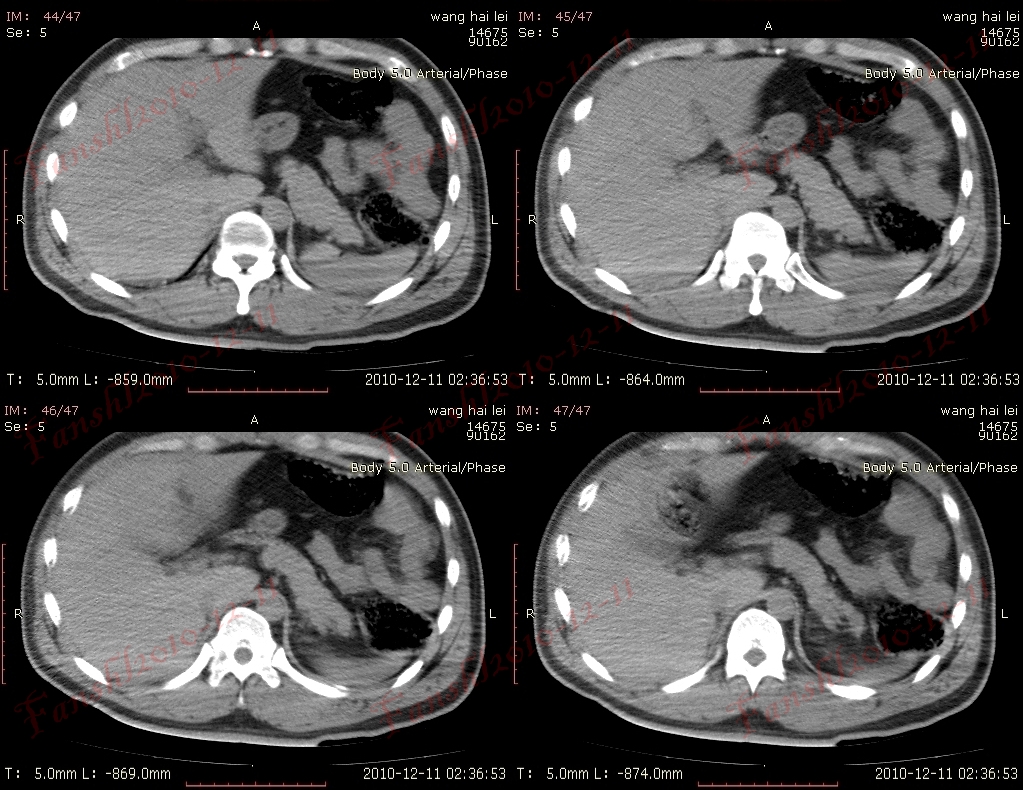

1、靶征(肠套叠)

是肠套叠最常见的特征性CT征像,为肠套叠长轴与CT扫描层面垂直时的表现,反映了套叠的各层肠壁、肠腔及肠系膜间的关系。典型排列为自外向内分别代表鞘部外层肠壁、鞘部肠腔内造影剂、鞘部内层肠壁、偏心性套入部肠系膜、套入部肠壁、套入部肠腔内造影剂。

肠套叠指:一段肠管及与其相连的肠系膜(套入部)被套如其相连的一段长管内(鞘部),导致肠内容物通过阻碍。婴儿由于大肠与小肠管径之比例相差大。故小肠易陷入大肠而被套牢。少数肠套叠可能来自某些器质性病变如美凯尔憩室、肠息肉、异位胰腺小结、血管瘤、异物、复制肠管、淋巴增生、肿瘤、寄生虫等,其中以美凯尔憩室最多,过敏性紫斑也常会合并肠套叠,大于2岁的小孩发生肠套叠,一定要考虑到这些病变。大于5岁的病例中,则以淋巴瘤为最多;成人肠套叠小肠多见,常伴发良性病变;结肠型肠套叠则更多由恶性病变继发。良性病变有脂肪瘤、平滑肌瘤、血管瘤、神经纤维瘤、腺瘤样息肉、美克尔憩室、术后粘连机场动力性病变等;恶性病变有转移瘤、腺癌、类癌、淋巴瘤及平滑肌肉瘤等。由于肠套叠长轴与CT扫描层面的角度不同,表现各异。

如扫描层面和迂曲的肠道相平行时,表现为彗星尾征或肾形征:即套叠近端肠系膜血管牵拉聚拢的征象。一般情况下,慧星尾征均与肾型肿块相伴出现。该肾形肿块为套鞘部游离缘与套入部近端肠管及肠系膜的CT斜切面图像,其中游离的套鞘呈弧形围绕套入部,形状若肾轮廓外形,而套入部近端肠管、肠系膜形状若肾蒂。此时,所谓慧星尾征的组成还应包括套入近端肠管。如果套叠的肠管与CT扫描垂直,则呈靶形征,即肿块影表现为圆形或类似环形。通常在肿块内可分辨出层样结构,推测可能是继发于套入部和鞘部间的液体或是肠壁水肿造成密度对比,类似同心圆形;当套入部肠壁显著水肿坏死或套入部肿瘤周围浸润累及肠系膜,肠系膜血管及脂肪、套叠时间较长,套入部系膜血管受挤压时,静脉血液回流障碍,套入部肠壁充血水肿、变硬,形成不完全性肠梗阻,套叠以上肠管蠕动增强,可引起代偿性肠管扩张肥厚,并可见肠系膜连同其血管纠集、扭曲,形成“漩涡征”。